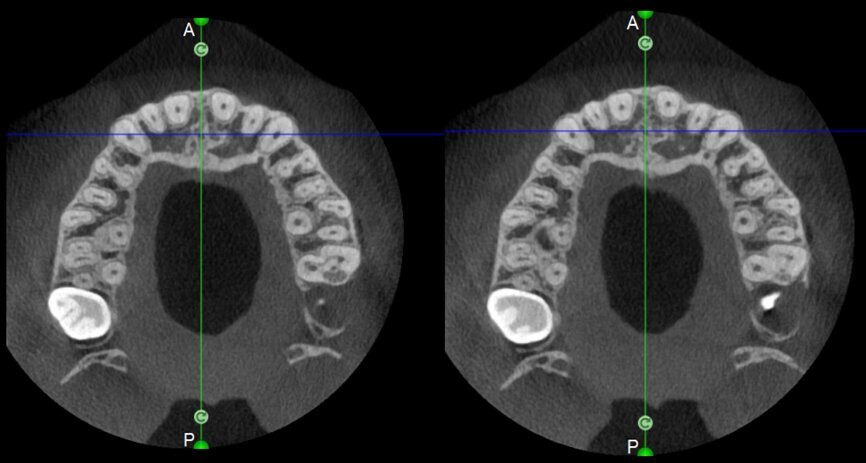

The case with which I would like to start my clinical review is a perfect example of how difficult it is to establish the origin of the patient’s symptoms on the basis of an intraoral radiograph alone. Not only does the 2D study fail to establish with certainty the presence of a lesion, but more importantly, it is impossible to establish the size, morphology and type of the lesion. An analysis of the 3D imaging, however, provides a clear picture of the clinical situation: the coronal and sagittal slices revealed the presence of a large lesion extending from the apex of the mesial root of this molar to the furcation, while the axial slices allow us to conduct a precise analysis of the endodontic anatomy and, in particular, the shape of the mesial root, which in this case was fused with the palatine root. A full overview of the case can, therefore, guide the decision-making process and direct the treatment plan towards a specific type of treatment (Figs. 1–4).